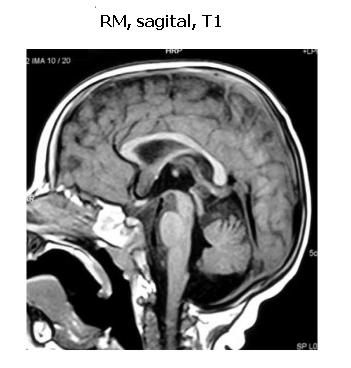

En la resonancia magnética (RM) de cráneo: parénquima encefálico de morfología conservada con adecuada distribución de la sustancia blanca y gris. En la sustancia blanca de centros ovales se identifica alteración en la intensidad de la señal, caracterizada por hipointensidad en T1 e hiperintensidad en las secuencias ponderadas en T2. Esta alteración es bilateral y simétrica, sin efecto de masa, compatible con desmielinización (figuras 2 y 3).

Distintos autores sostienen que la RM de cráneo en oportunidades resulta el estudio de elección frente al planteo etiológico de un error congénito del metabolismo tal como se evidenció en este caso. Su resultado fue muy orientador de una enfermedad desmielinizante, al ser analizado junto a la historia clínica, elementos del examen físico, disminución de velocidad de conducción e hiperproteinirraquia. Con estos elementos, se plantea diagnóstico de probable leucodistrofia. Entre ellas, en primer lugar enfermedad de Krabbe y en segundo lugar leucodistrofia metacromática. En este caso se confirmó el diagnóstico de EK a través de la dosificación de la actividad galactocerebrósido-b-galactosidasa en leucocitos.

Frente a un cuadro clínico sugestivo de EK la investigación inicial debe incluir el examen del LCR y estudio de neuroimagen. Los estudios iniciales para valoración metabólica básica suelen ser normales (12). A nivel del LCR se puede encontrar en la mayoría de los casos una hiperproteinorraquia, a niveles cercanos a 100 mg/dl como en este caso (6). La resonancia magnética (RM) de cráneo muestra lesiones de atrofia, principalmente donde la mielinización es más temprana. Lesiones simétricas de sustancia blanca con afectación periventricular y atrofia cerebral progresiva también son descritas (7). Las imágenes de atrofia son tardías en la evolución de la enfermedad. Lo más característico en la RM en el primer año de vida es el aumento de la señal en T2 a nivel de la sustancia blanca profunda y periventricular, particularmente en el sector frontal posterior y parietal anterior y de los núcleos profundos y de la sustancia blanca del cerebelo (14).

La RM con espectroscopia permite la detección del compromiso de sustancia blanca antes que ésta sea evidente por la RM convencional. En la EK la espectroscopía presenta en la sustancia blanca elevaciones de los niveles de mioinositol, colina y creatina, junto a la disminución de N-acetilaspartato. En forma inconstante, puede observarse un aumento del pico de lactato (14). En este caso se observó una disminución de la N-acetilaspartato, con aumento de la colina y de los picos de lactato. Estos hallazgos reflejan el proceso de desmielinización, proliferación de las células de la glía y destrucción neuroaxonal (6).